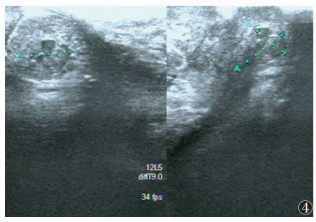

超声共发现病灶区101个(图 1~4),敏感度79.5%,超声诊断与手术结果对照见表 1。经阴道超声诊断的最低敏感度(64.4%)和准确率(79.7%)在阴道,最高敏感度(94.6%)和准确率(97.5%)在直肠子宫陷凹。

| 图 4 48岁,直肠下段病灶,主诉排便疼痛不畅,超声示直肠壁混合回声区,边界不清,内见细小液性回声区,能量多普勒成像示散在杆状血流信号 |

DIE病灶超声表现:呈结节状、片状或不规则形,边界欠清、不规整。可与周边组织粘连;多为低回声区,偶为等、高回声区,内部回声不均匀,可见细小无回声区,透声欠佳,CDFI可见部分病灶散在短杆或点状的穿枝型血流病灶(17/101,16.8%)。

各部位DIE病灶的诊断要点:①宫骶韧带表现为宫颈下段两侧旁结节样或条索样低不规则回声区;宫旁组织、子宫浆膜面病灶呈不规则片状或斑块状低回声,注意与子宫浆膜下肌瘤鉴别。②超声直接在输尿管周围或内部发现明显病灶较困难,伴输尿管扩张的DIE可增加诊断率,本研究中2例均因输尿管扩张而诊断,但需注意排除,如结石、先天性狭窄等梗阻因素。③膀胱病灶由于尿液透声窗衬托,诊断敏感度较高,病灶常见于后壁,呈低回声结节,可局限于膀胱浆膜面,超声可评估病变的侵犯深度。④本研究中经阴道超声对直肠子宫陷凹病灶诊断敏感度和准确率最高,与文献[8]报道一致,直肠子宫陷凹粘连封闭为DIE显著特征,也可表现为不规则低回声区,与子宫后壁分界不清。⑤阴道、直肠、阴道直肠隔DIE病灶常经妇检首先发现,经阴道超声诊断敏感度偏低,表现为局部不规则低回声区,探头触痛,检查中注意分清三者毗邻结构关系,精确定位病灶侵犯部位。直肠病灶常与宫颈后区病变粘连,造成直肠子宫陷凹闭锁。⑥DIE超声表现虽有一定的特征性,但也需与盆腔脏器恶性肿瘤鉴别。DIE病灶对腹膜脏器浸润是从外(浆膜层)向内(肌层),而肿瘤对肠壁脏器的浸润则是自内(黏膜层)向外(浆膜层)。直肠子宫陷凹病灶需与肿瘤的腹膜转移灶鉴别,两者表现相似,但肿瘤结节的外形较规则,CDFI血流信号丰富,而DIE形态多呈不规则斑片状,CDFI血流信号稀少;且转移瘤常伴腹腔积液,结合其他辅助检查可发现相关原发肿瘤,有助于确诊。

各部位DIE病灶的诊断要点:①宫骶韧带表现为宫颈下段两侧旁结节样或条索样低不规则回声区;宫旁组织、子宫浆膜面病灶呈不规则片状或斑块状低回声,注意与子宫浆膜下肌瘤鉴别。②超声直接在输尿管周围或内部发现明显病灶较困难,伴输尿管扩张的DIE可增加诊断率,本研究中2例均因输尿管扩张而诊断,但需注意排除,如结石、先天性狭窄等梗阻因素。③膀胱病灶由于尿液透声窗衬托,诊断敏感度较高,病灶常见于后壁,呈低回声结节,可局限于膀胱浆膜面,超声可评估病变的侵犯深度。④本研究中经阴道超声对直肠子宫陷凹病灶诊断敏感度和准确率最高,与文献[8]报道一致,直肠子宫陷凹粘连封闭为DIE显著特征,也可表现为不规则低回声区,与子宫后壁分界不清。⑤阴道、直肠、阴道直肠隔DIE病灶常经妇检首先发现,经阴道超声诊断敏感度偏低,表现为局部不规则低回声区,探头触痛,检查中注意分清三者毗邻结构关系,精确定位病灶侵犯部位。直肠病灶常与宫颈后区病变粘连,造成直肠子宫陷凹闭锁。⑥DIE超声表现虽有一定的特征性,但也需与盆腔脏器恶性肿瘤鉴别。DIE病灶对腹膜脏器浸润是从外(浆膜层)向内(肌层),而肿瘤对肠壁脏器的浸润则是自内(黏膜层)向外(浆膜层)。直肠子宫陷凹病灶需与肿瘤的腹膜转移灶鉴别,两者表现相似,但肿瘤结节的外形较规则,CDFI血流信号丰富,而DIE形态多呈不规则斑片状,CDFI血流信号稀少;且转移瘤常伴腹腔积液,结合其他辅助检查可发现相关原发肿瘤,有助于确诊。